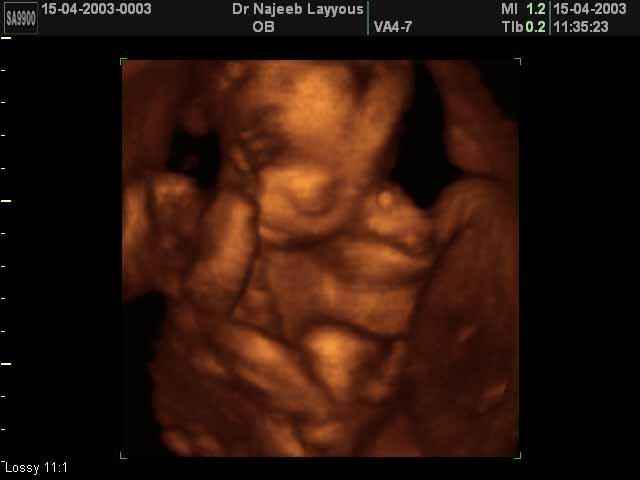

3D second trimestre échographie Photos de numérisation - deuxième partie de la grossesse | Dr N Layyous

3D second trimestre échographie Photos de numérisation - deuxième partie de la grossesse